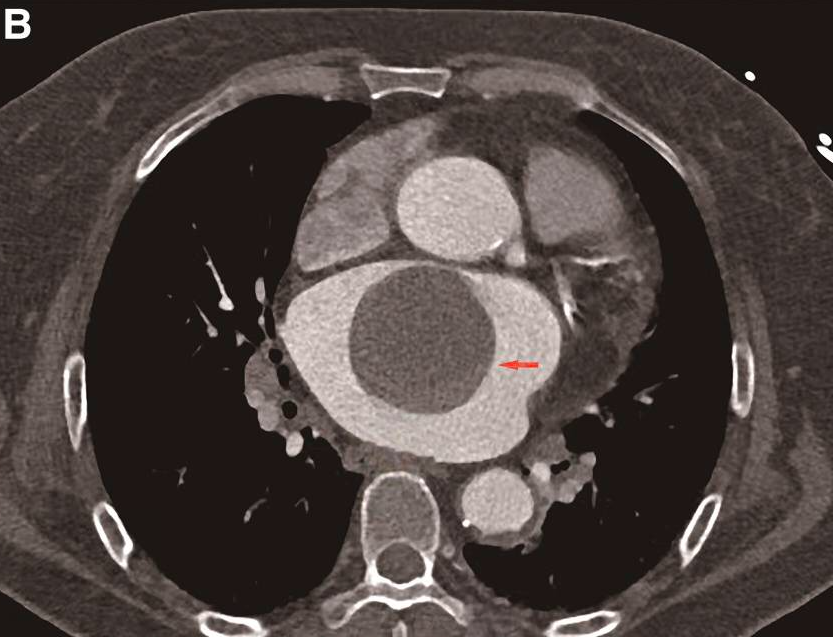

左心房CT显示,扩大的左心房内存在一个巨大的、光滑的、边界清楚的充盈缺损,与房间隔中部紧密相连。在舒张期,肿物位于二尖瓣口附近(图1B和视频)。

B 患者CT显示左心房内巨大的肿物(箭头所指为左心房内的肿物)。